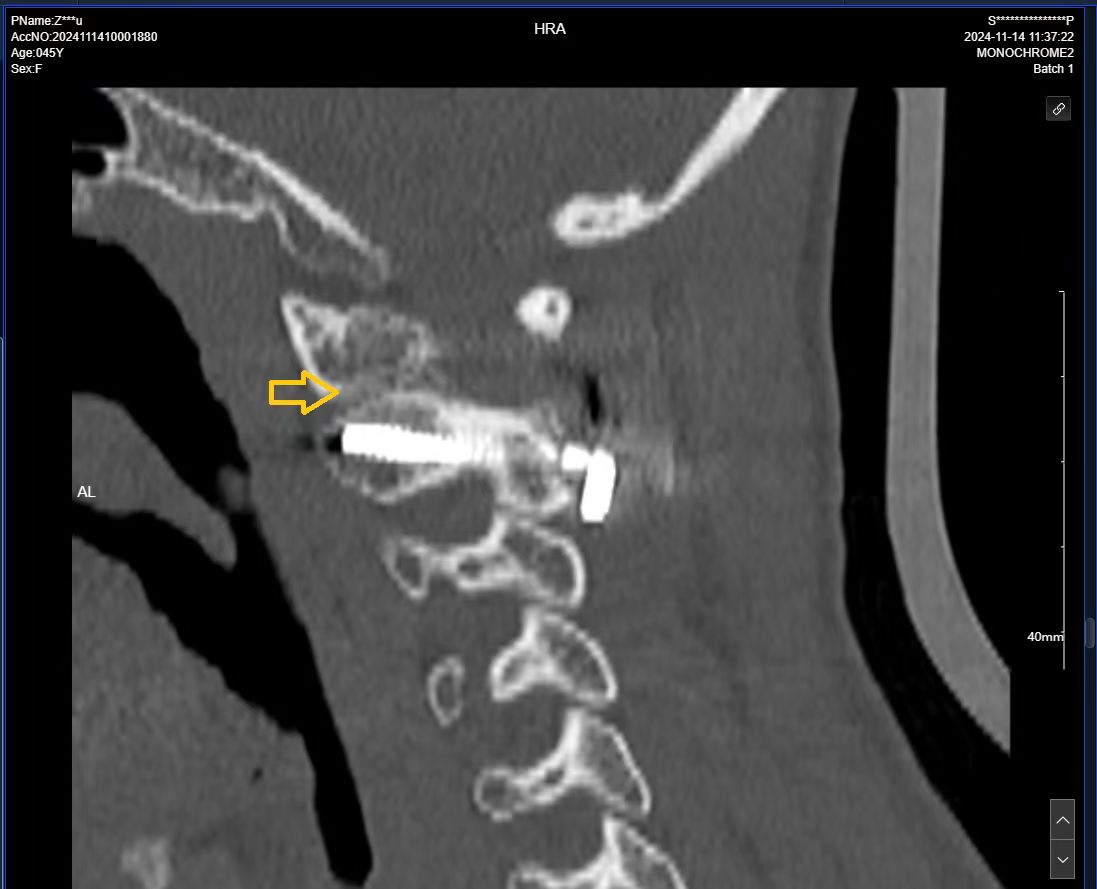

二次手术#

• 日期:2024.06.14

• 医院:北三医院

• 主刀:王超

• 术后状况:手脚无力的症状消失,低头时间久了脖子手术的地方酸痛。

• 术后影像:

• 2024.11.07,复查,对位良好。